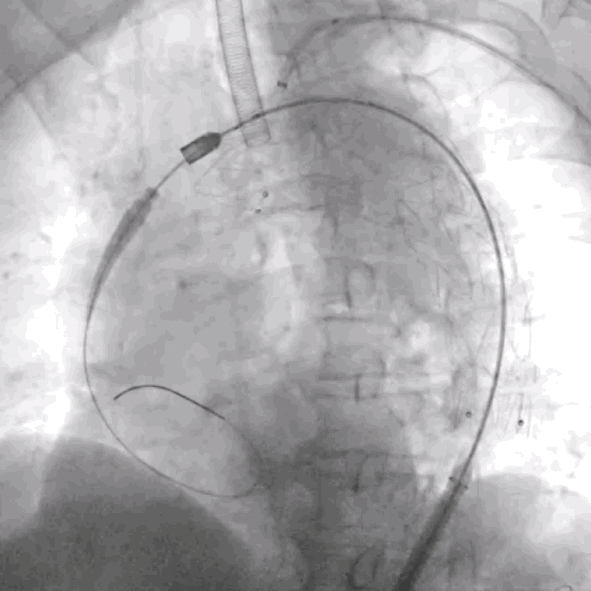

5. 经左肱动脉导入VBX(10mm*39mm)至开窗口释放,并使用10mm*20mm Mustang球囊行支架内扩张。

泥鳅导丝怎么用符伟国/王利新教授团队:0.035"普通泥鳅导丝进行胸主动脉弓上分支原位开窗的病例分享_https://www.jmylbn.com_新闻资讯_第19张

确认LSA及椎动脉开口位置

泥鳅导丝怎么用符伟国/王利新教授团队:0.035"普通泥鳅导丝进行胸主动脉弓上分支原位开窗的病例分享_https://www.jmylbn.com_新闻资讯_第20张

释放10mm*39mm VBX球扩支架

泥鳅导丝怎么用符伟国/王利新教授团队:0.035"普通泥鳅导丝进行胸主动脉弓上分支原位开窗的病例分享_https://www.jmylbn.com_新闻资讯_第21张

使用10mm*20mm球囊扩张分支支架

泥鳅导丝怎么用符伟国/王利新教授团队:0.035"普通泥鳅导丝进行胸主动脉弓上分支原位开窗的病例分享_https://www.jmylbn.com_新闻资讯_第22张

RAO位置造影大支架封闭良好,无内漏

泥鳅导丝怎么用符伟国/王利新教授团队:0.035"普通泥鳅导丝进行胸主动脉弓上分支原位开窗的病例分享_https://www.jmylbn.com_新闻资讯_第23张

LAO位置造影左锥动脉血流良好

6. 最终造影:主动脉弓部瘤病变显影消失,主体支架形态良好,分支支架通畅,左椎动脉显影良好。